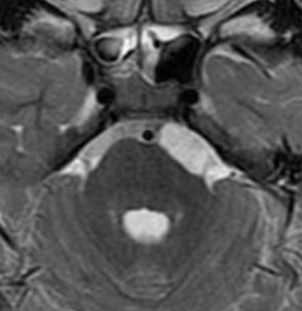

МРТ головного мозга. Аксиальная Т2-взвешенная МРТ. Фрагмент ММУ. Холестеатома слева.

Вестибулокохлеарный нерв (VIII) состоит из 4 пучков. Опухоли происходят обычно из вестибулярной его части. Шваннома - инкапсулированная доброкачественная (градация 1) опухоль, происходящая из дифференцированных неопластических шванновских клеток оболочек периферических нервов. Невриномы ММУ составляют около 3% опухолей головного мозга. Часть шванном (двухсторонние слуховых нервов) связана с НФ 2 типа. Пик частоты между 40 и 60 годами. Растут медленно и крайне редко малигнизируются. Клинические проявления связаны с нарушением функции нерва и компрессией ствола. Шваннома может происходить из любого отрезка по ходу нерва и хорошо прослеживается при МРТ области ММУ. Невринома видна как на Т2-взвешенных, так и на Т1-взвешенных МРТ в виде округлого образования. Невриномы хорошо и равномерно усиливаются после МРТ с введением контрастного вещества. Невриномы области цистерны могут иметь компонент во внутреннем слуховом проходе, особенно, хорошо видимый при МРТ головного мозга с контрастированием. Изредка встречаются невриномы полностью расположенные внутри канальца. Они составляют наибольшую диагностическую сложность при МРТ, требуют тонких срезов и контрастирования. Менингиомы ММУ обычно типично расположены и при МРТ имеют характерную форму и типичные черты при МРТ с контрастированием. Однако редко встречаются внутриканальцевые менингиомы. При МРТ они неотличимы от неврином. Холестеатомы при МРТ имеют смешанную интенсивность сигнала, в зависимости от их содержимого. На диффузионно-взвешенных МРТ холестеатомы обычно яркие.